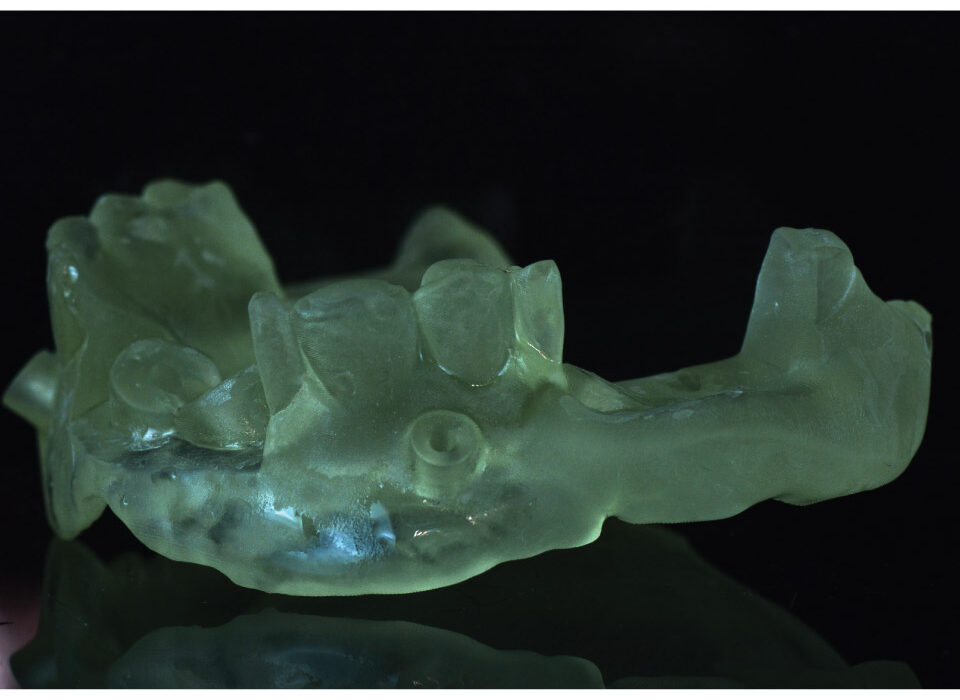

Surgical Guides

Surgical Guide is a digital tool that ensures accurate positioning and angulation of implants, which is crucial for the success and longevity of the implant. We fabricate different types of surgical guides, including tooth-borne, mucosa-borne, and bone-borne guides i.e stackable.